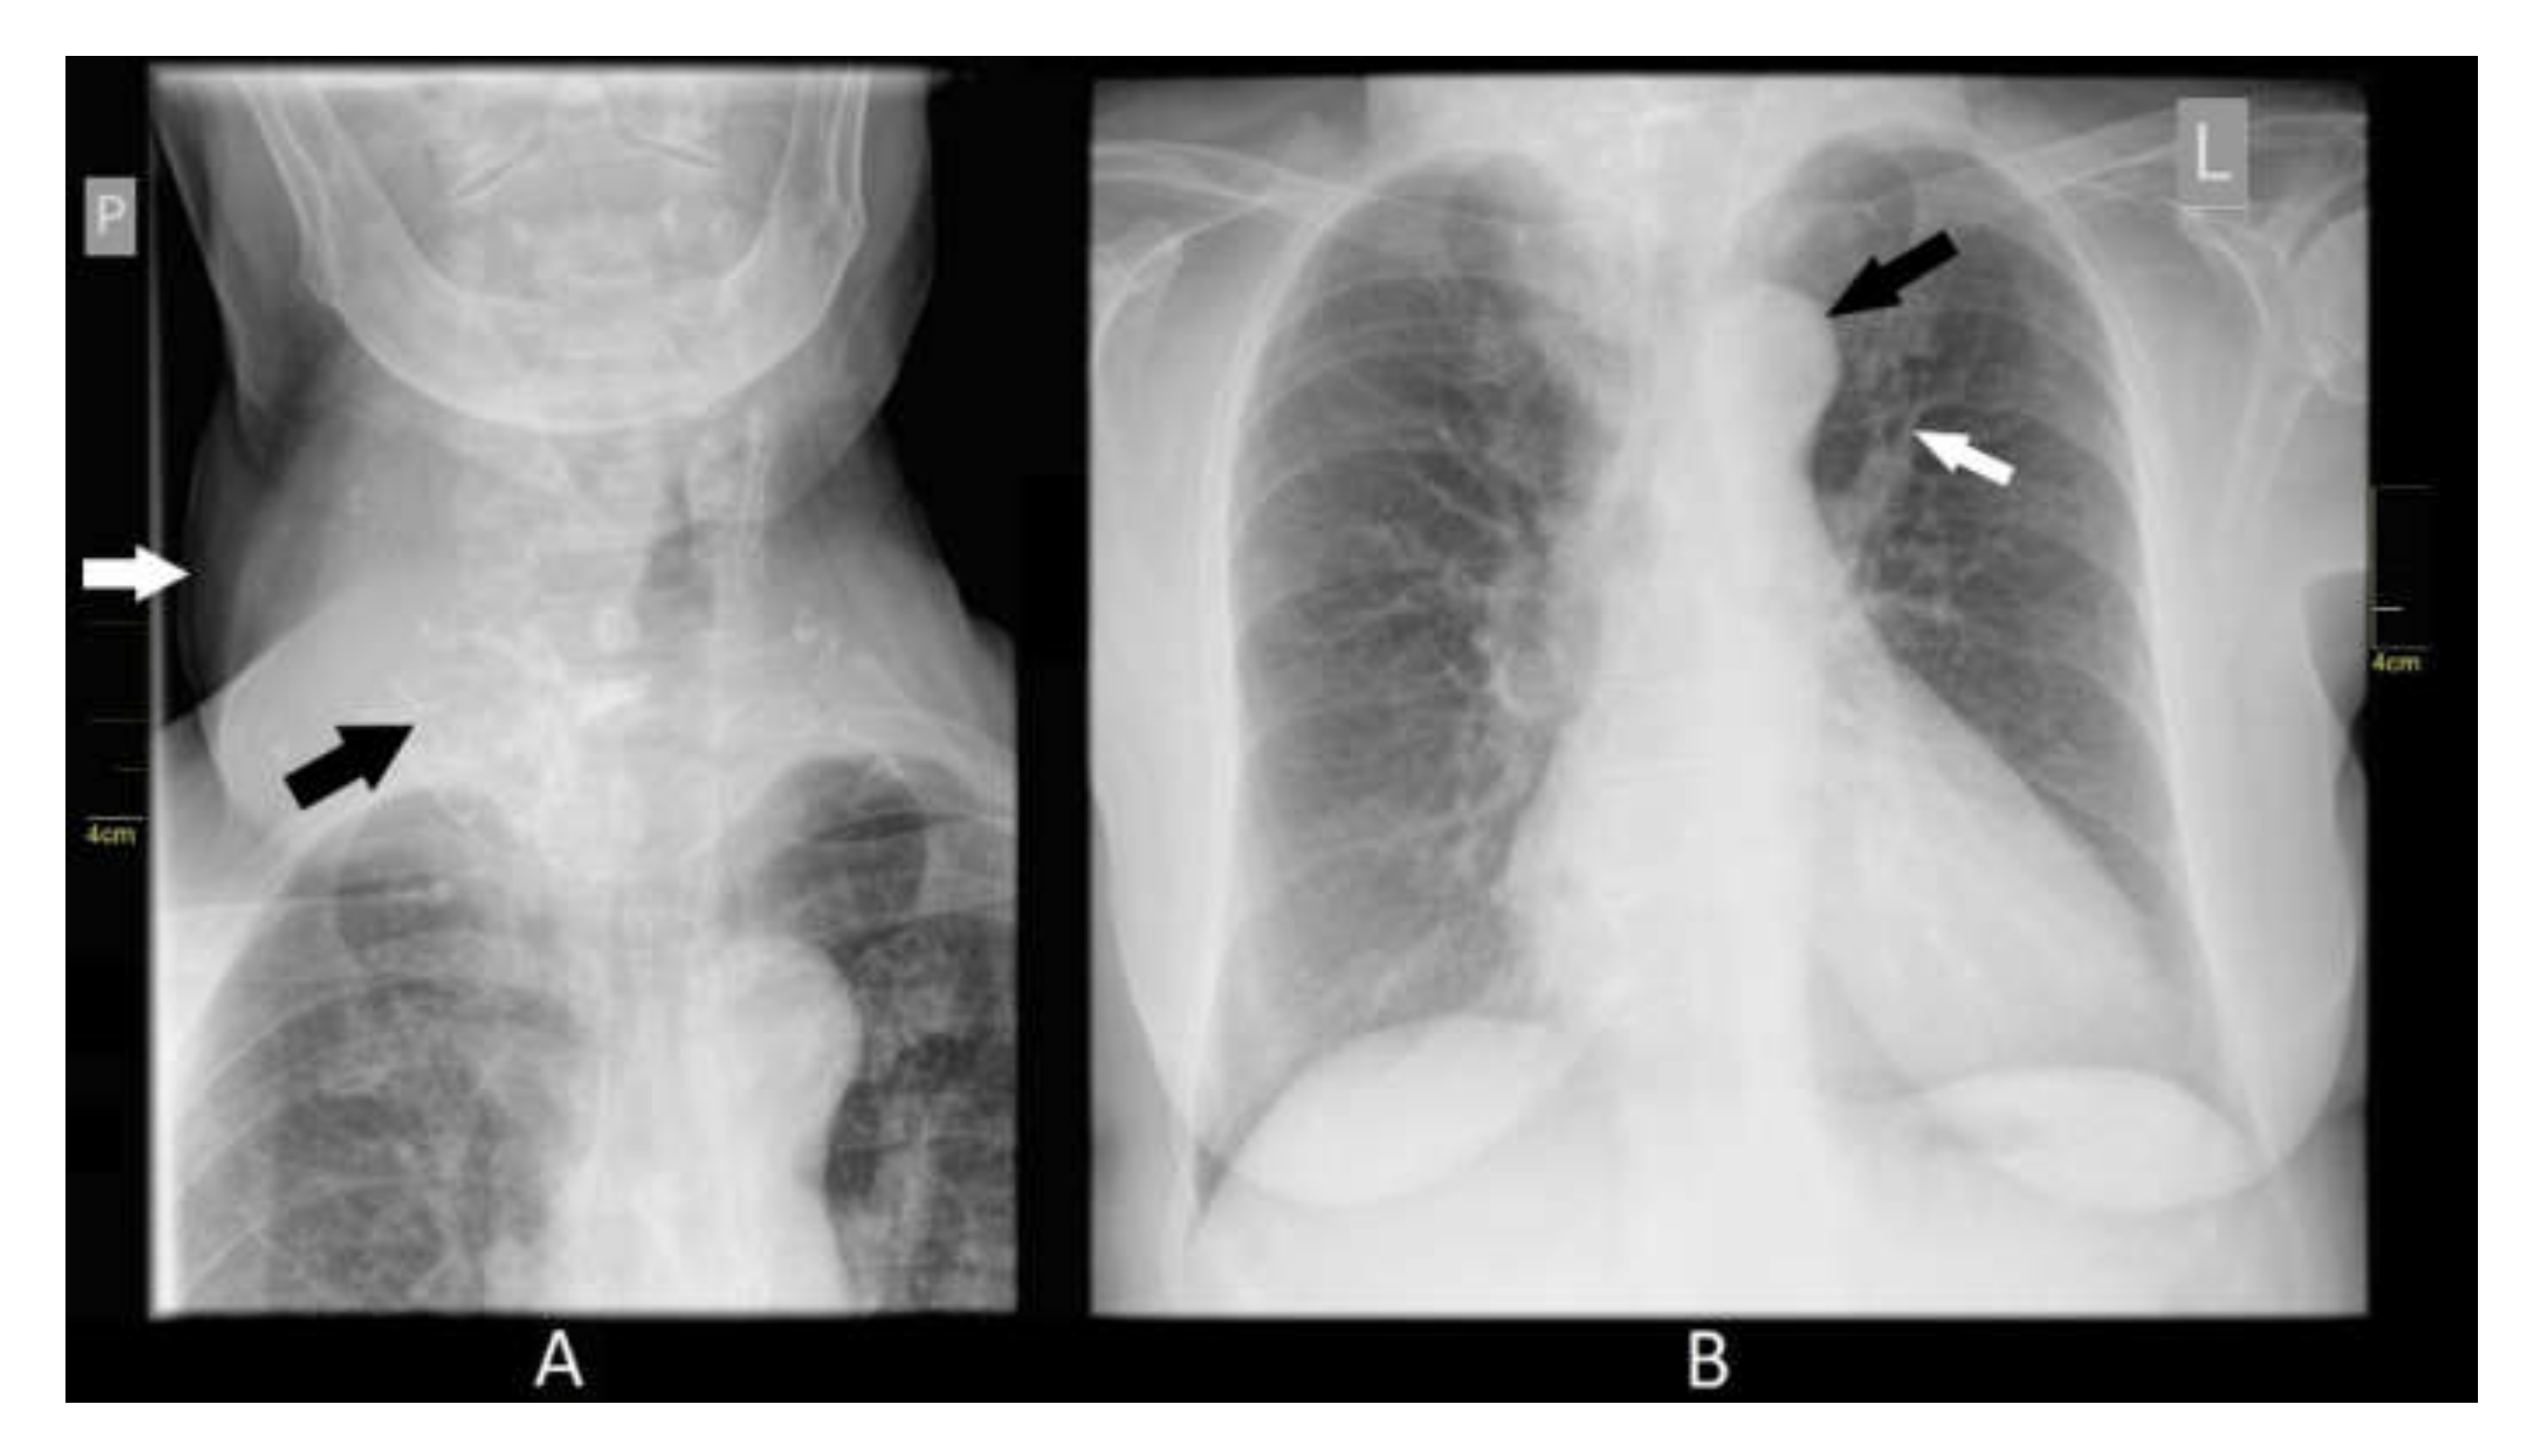

2. Case Presentation